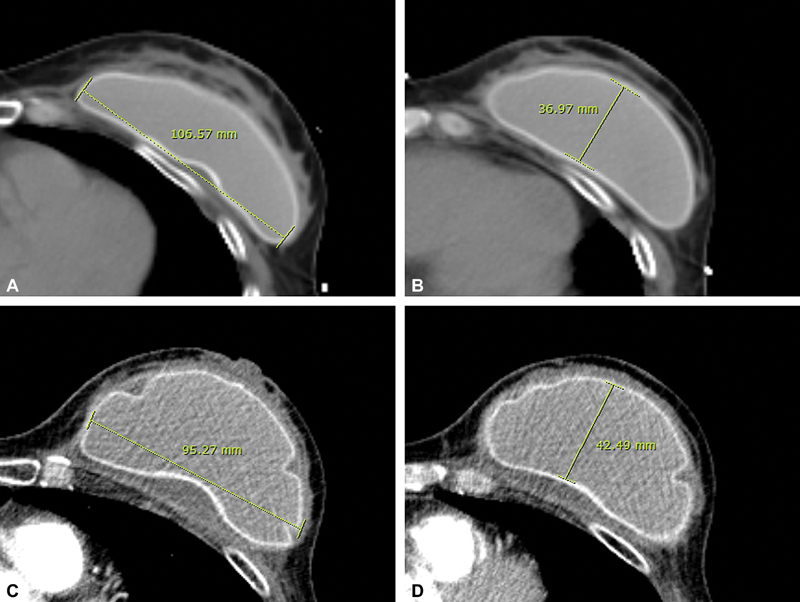

Methods: We enrolled 94 patients who underwent breast reconstruction using implants and underwent periodic chest CT scans. We categorized them into two groups: Baker grade I or II ( n  = 72) and Baker grade III or IV ( n  = 22). We analyzed the CT scans to assess changes in the implant base and projection.

Results: In the Baker grade III or IV groups, it was confirmed that the ratio of projection to base increased after capsular contracture compared with before contracture. On the other hand, there was no significant change in the ratio of projection to base in the Baker grade I or II groups.